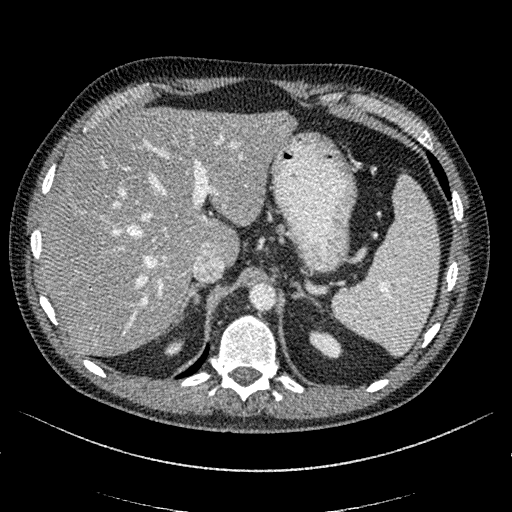

![]() |

| 0.31 [0.33] | 2.94 [2.83] | 0.12 [0.00] |

| 2.02 [2.00] | 3.82 [3.83] | 3.85 [4.00] |

Fig. 3 visualizes sample abdominal CT images with varying quality levels from the test set. The predicted IQA scores show strong agreement with the reference scores across different noise and artifact intensities, which indicates the robustness of CAP-IQA in accurately quantifying CT image quality. The kernel density plot in Fig. 4 illustrates how prediction residuals are distributed across different IQA score groups. All curves are centered near zero, indicating balanced predictions without systematic bias toward any specific quality range. Moreover, the box plot presents the distribution of absolute prediction errors across different IQA score groups. The median errors remain low and consistent, showing that CAP-IQA performs reliably across all quality levels, with minimal variations and stability in predictions. Consistent with this interpretation, our pairwise testing using the Kruskal-Wallis H-test further confirms that there is no significant difference in performance for different IQA score groups (p-value 0.38).